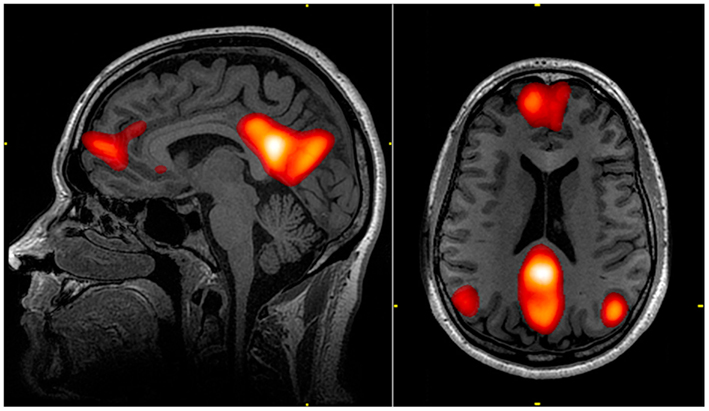

By measuring BOLD data and functional connectivity when people are at rest, researchers now know that the default mode network consists of regions including the medial prefrontal cortex, the posterior cingulate cortex, the precuneus, and bilateral parietal cortex2,3 that have high functional connectivity with each other (Figure 1). This network of regions has high activity when the brain is at rest, and activity decreases when most goal-directed tasks begin4. Other networks, in contrast, are less active at rest and become activated by tasks that require attention or cognitive work.

Figure 1 from John Graner via Wikimedia Commons, public domain https://commons.wikimedia.org/wiki/File:Default_mode_network-WRNMMC.jpg